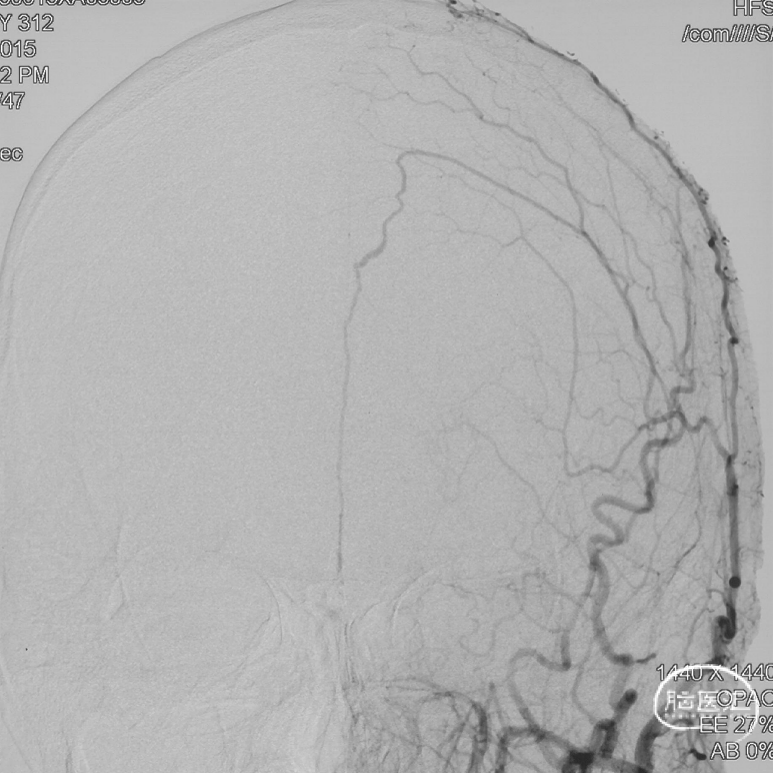

通过Marathon微导管注入Onyx 18,胶向瘘口弥散,并弥散至镰前动脉。

停顿后进一步注射Onyx18,此时胶向对侧筛前动脉弥散,直至闭塞瘘口和引流静脉起始端。

最终造影瘘口完全不显影。

双侧脉络膜染色正常。

Onyx胶铸型进一步显示了瘘的结构。AFA:镰前动脉;AEA:筛前动脉;PEA:筛后动脉;DV:引流静脉。